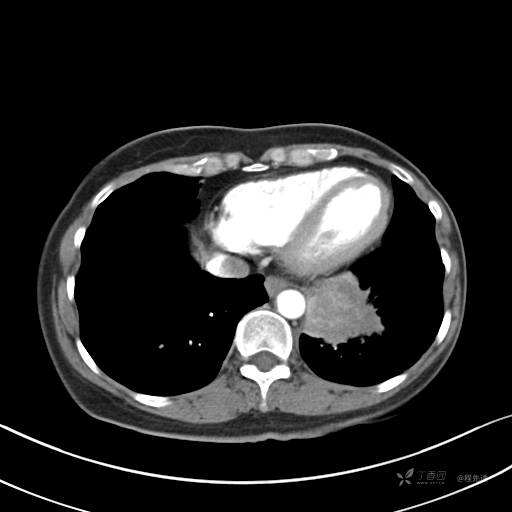

增强动脉期

动脉期CT值约74HU